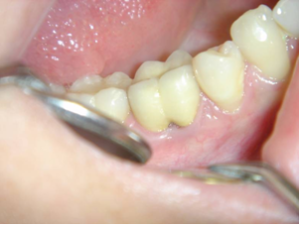

Nettoyage inter-radiculaire.

Reprise du traitement endodontique , séparation des racines et curetage inter-radiculaire.